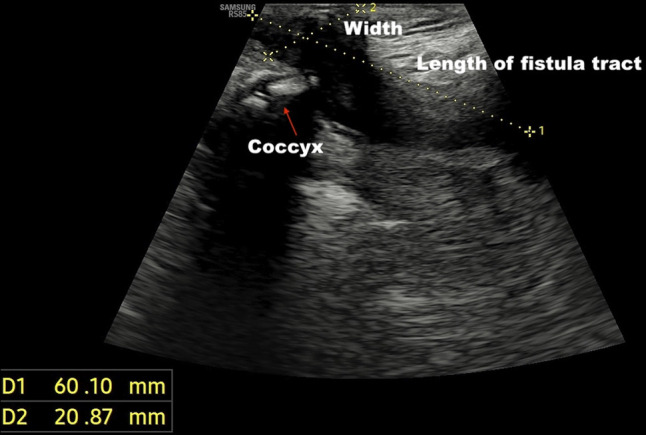

Abstract Image